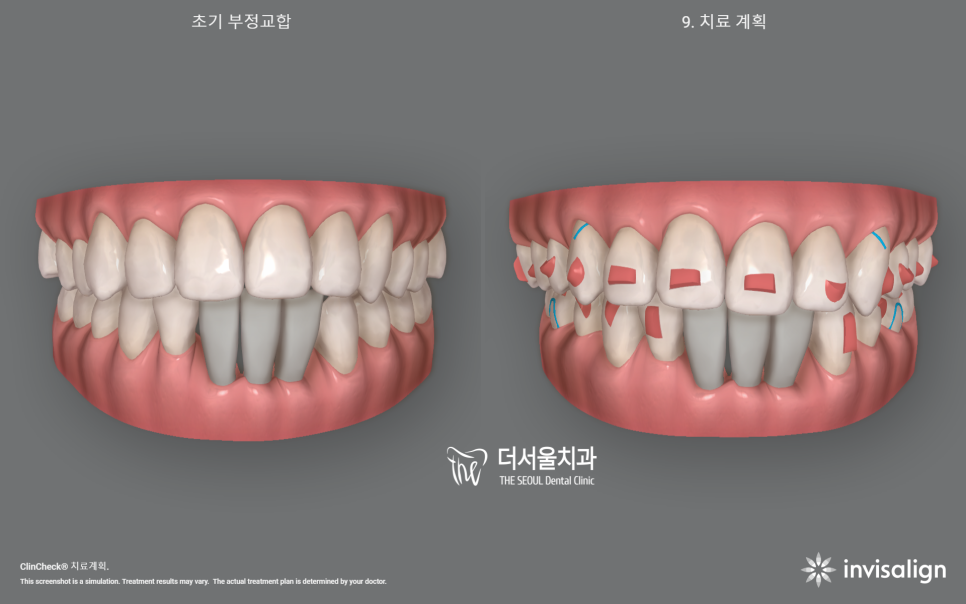

2. 인비절라인 시뮬레이션

시뮬레이션을 영상으로 보니 신기하죠?

인비절라인 클린첵 시뮬레이션을 하면

이렇게 치료 전, 후 를 나눠서 어떤식으로

치아들이 이동이 되면서 빈 틈이 만들어지며

다시 그 빈틈을 메꾸려 다른 치아들을

이동시켜줘야 되는지 술자에게

많은 정보들을 제공합니다.

물론, A.I 기반이라서 최종 수정은

담당 주치의가 직접 진행을 해야 되죠.

이 환자의 경우 임플란트 시술을

해야 되는 상황이라서 우선 임플란트를

심을 수 있는 환경부터 조성해야 됩니다.

이런 것 또한 미리 시뮬레이션에

데이터를 집어넣어서 임플란트의

예상 위치에 따른 교정치료의 종점을

예상할 수 있습니다.